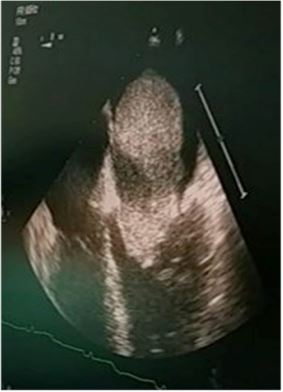

Patient’s vital signs were within normal ranges, his Electrocardiogram (ECG) showed sinus rhythm. The myxoma was found incidentally on Transthoracic Echocardiogram (TTE) and the size of the mass was confirmed to be 5 cm x 5 cm attached to the interatrial septum with one third of the mass extending to the left ventricle (Figure 1). His left ventricle A normal ejective fraction LVEF was 50-55%, with mild Mitral Regurgitation (MR), moderate to severe Mitral Stenosis (MS) and Tricuspid Tegurgitation (TR). It was also showed high Pulmonary Arterial Systolic Pressure (PASP) with 73 mmHg. On computed Tomography (CT) of the thoracic region (CECT thorax), it showed a 5 cm x 4 cm x 3 cm large mass attached to the atrial septum in the left atrium.

Figure 1: TTE of patient showing left atrial myxoma of septal origin.